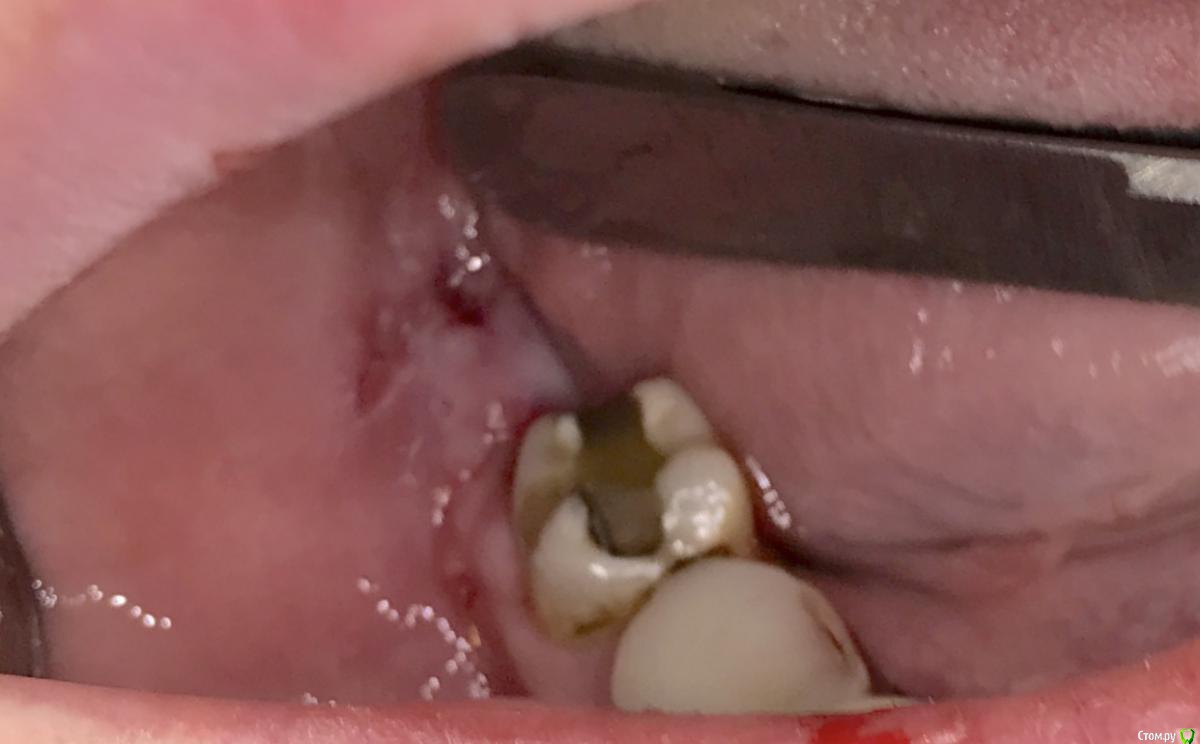

колесников Опубликовано 25 марта, 2017 Автор Поделиться Опубликовано 25 марта, 2017 Повторение-мать учения 1 Ссылка на комментарий

Irouil Опубликовано 25 марта, 2017 Поделиться Опубликовано 25 марта, 2017 Это язычный? Ссылка на комментарий

колесников Опубликовано 25 марта, 2017 Автор Поделиться Опубликовано 25 марта, 2017 Он Ссылка на комментарий

колесников Опубликовано 26 марта, 2017 Автор Поделиться Опубликовано 26 марта, 2017 (изменено) Вид через неделю. Швы удалены. Пациент как ни странно жив. Боли не испытывал ,3 дня был отек. Снимок "до". Изменено 26 марта, 2017 пользователем колесников Ссылка на комментарий